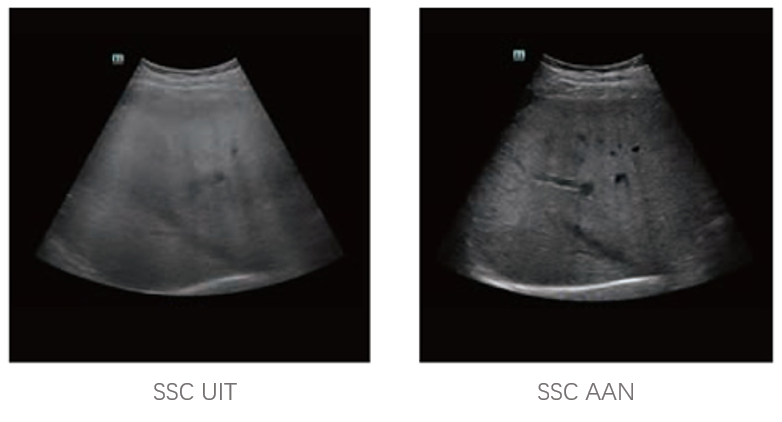

Sinds de oprichting van het bedrijf is Mindray voortdurend op zoek naar nieuwe manieren om het diagnostisch vertrouwen te vergroten. Resona 7 wordt aangestuurd door de meest revolutionaire ZONE Sonography?-technologie. Zijn nieuwe ZST+-tilt de kwaliteit van ultrasoundbeeldvorming naar een hoger niveau door middel van zoneacquisitie en kanaalgegevensverwerking.